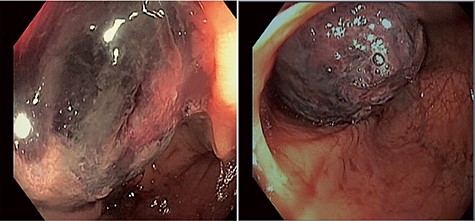

A 54-year-old man presented to his gastroenterologist with a 4-week history of worsening crampy abdominal pain associated with abdominal distention and obstipation. He was admitted urgently to the hospital after CT imaging revealed an evolving large bowel obstruction from transverse colonic intussusception likely secondary to a colonic mass lead point (Fig. 1). The patient underwent colonoscopy, but dusky nonviable mucosa was seen at the leading edge of the intussusceptum (Fig. 2), so no attempt was made to traverse it and the patient was taken for emergent surgical treatment. Using a hand-assisted laparoscopic approach, the cause of obstruction was confirmed to be a long segment of intussuscepted proximal transverse colon traversing the entire splenic flexure into descending colon, with a boggy mass acting as the lead point. The transverse colonic intussusceptum was carefully milked backward from within the descending colonic intussuscipiens to its natural anatomic position. Despite return of pink, viable colon appearance after a decompressive colotomy, some serosal abnormalities and congestion of the right colon from severe distention warranted its resection. An extended right hemicolectomy was performed with a distal transection margin 10 cm distal to the colonic mass origin, followed by stapled side-to-side, functional end-to-end ileocolonic anastomosis. The resected specimen was opened intraoperatively, revealing a large, pedunculated, polypoid mass with soft center consistent with colonic lipoma (Fig. 3). The patient recovered well, with return of bowel function on postoperative Day 3 prior to discharge home. Histopathology confirmed a 9.5 × 5.5 × 4.5 cm submucosal lipoma (Fig. 4) and 12 benign lymph nodes.

Colonoscopic images of the colonic intussusceptum with an ischemic, dusky mass lead point secondary to mucosal edema and venous congestion.